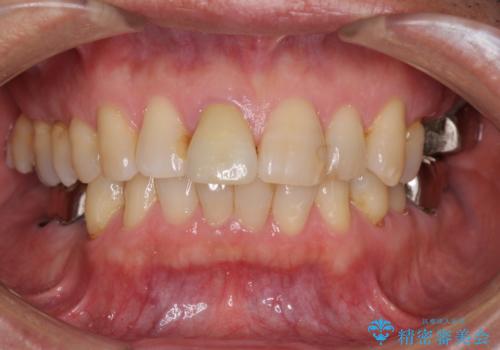

部分矯正期間中はアンカースクリューやフック、ゴムなどが粘膜にあたり、大変な思いをすることになりましたが、そのおかげでインプラント補綴した歯と最後方歯の位置が非常に良好となり、まるでご自身の歯のように咬むことができるようになりました。